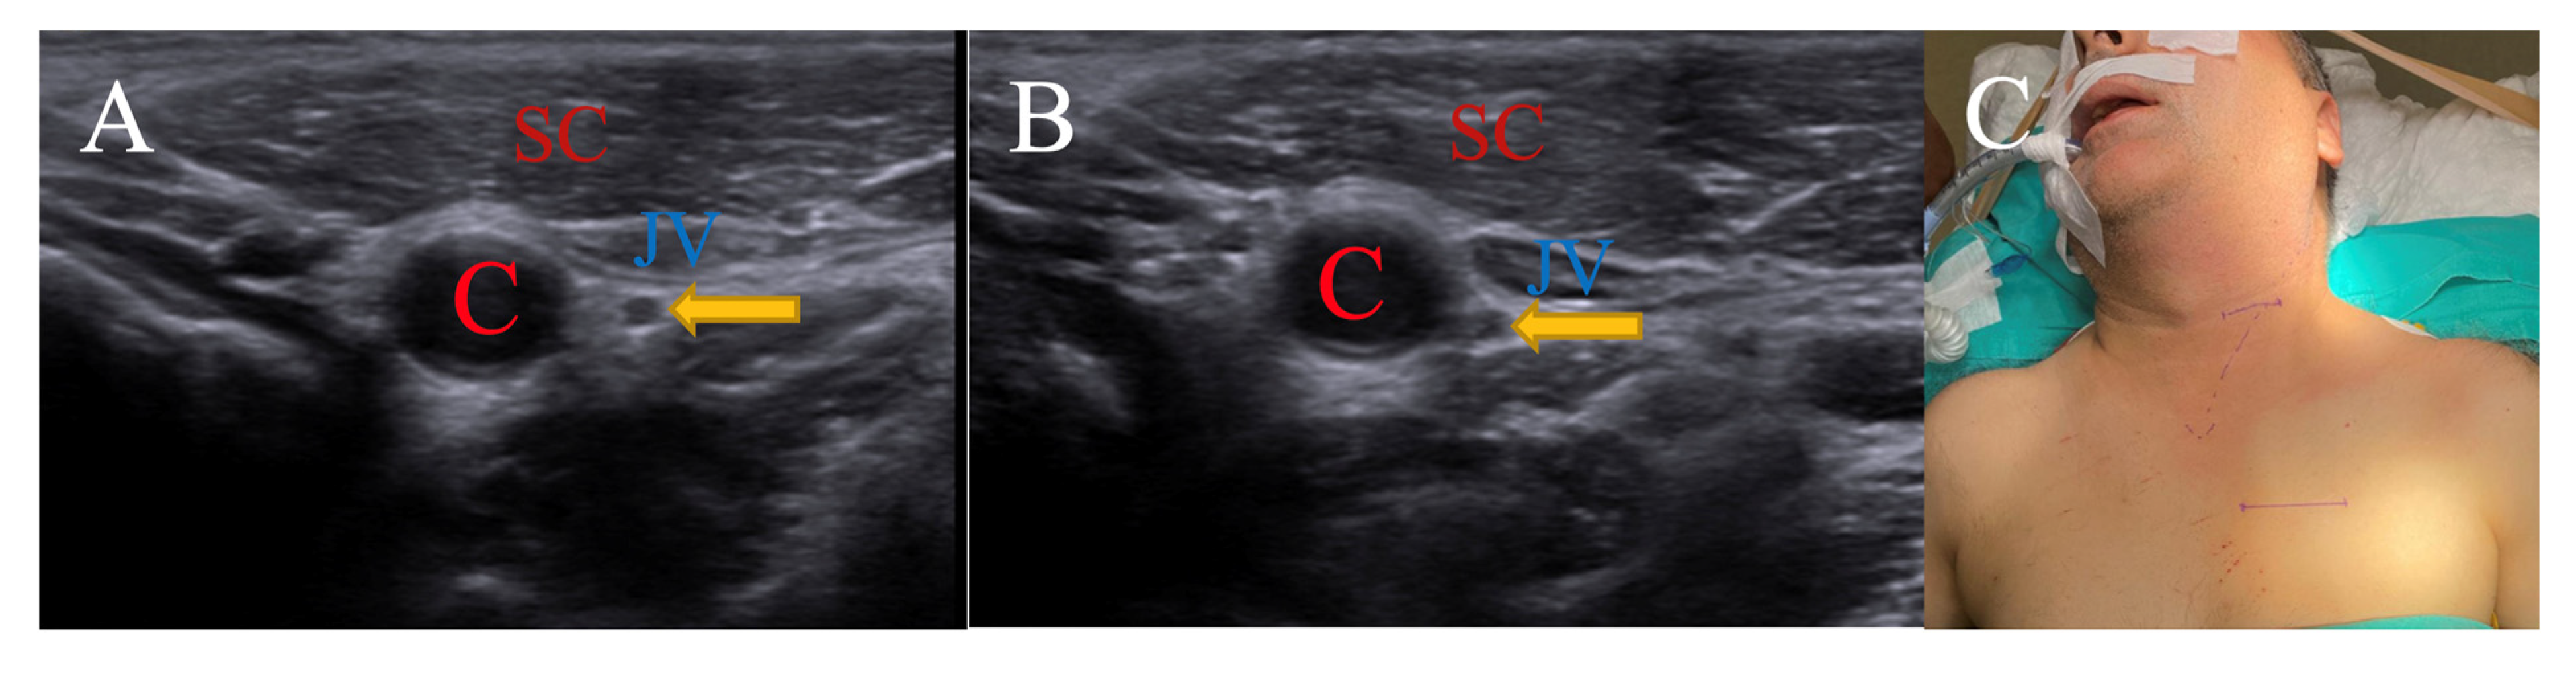

3.1.1. Contralateral Head Rotation for Nervus Vagus

| SCM | Sternocleidomastoid |

| C | Carotid artery |

| JV | Jugular vein |